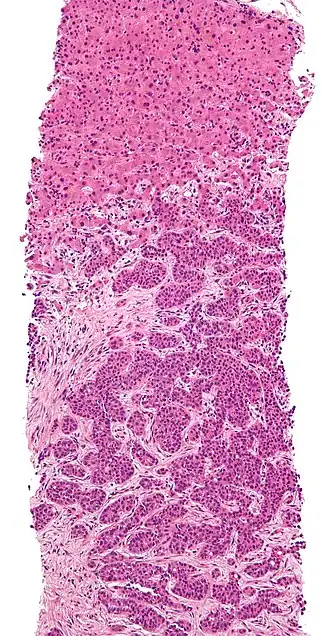

Squamous cell carcinoma occluding bronchus with metastasis to adjacent lymph node.